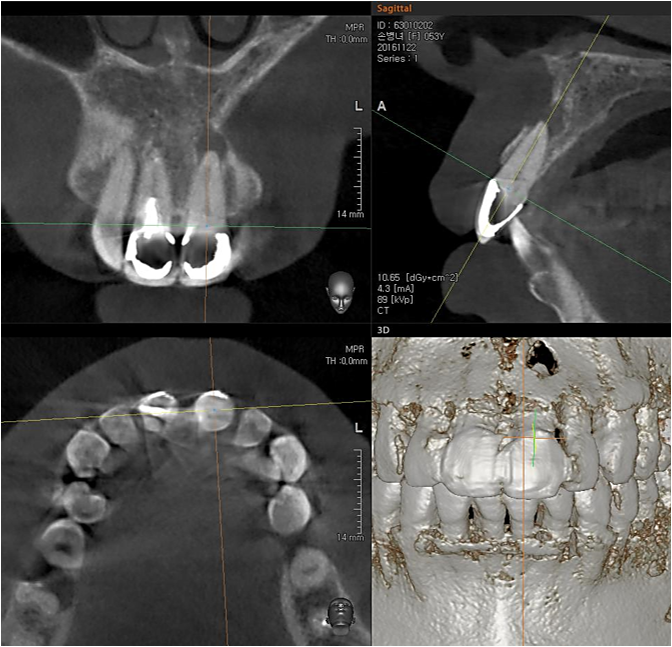

Apicorctomy /central incisor /GBR ; 6-year follow up.

<CJ SBN> Apicorctomy /central incisor /GBR ; 6-year follow up.